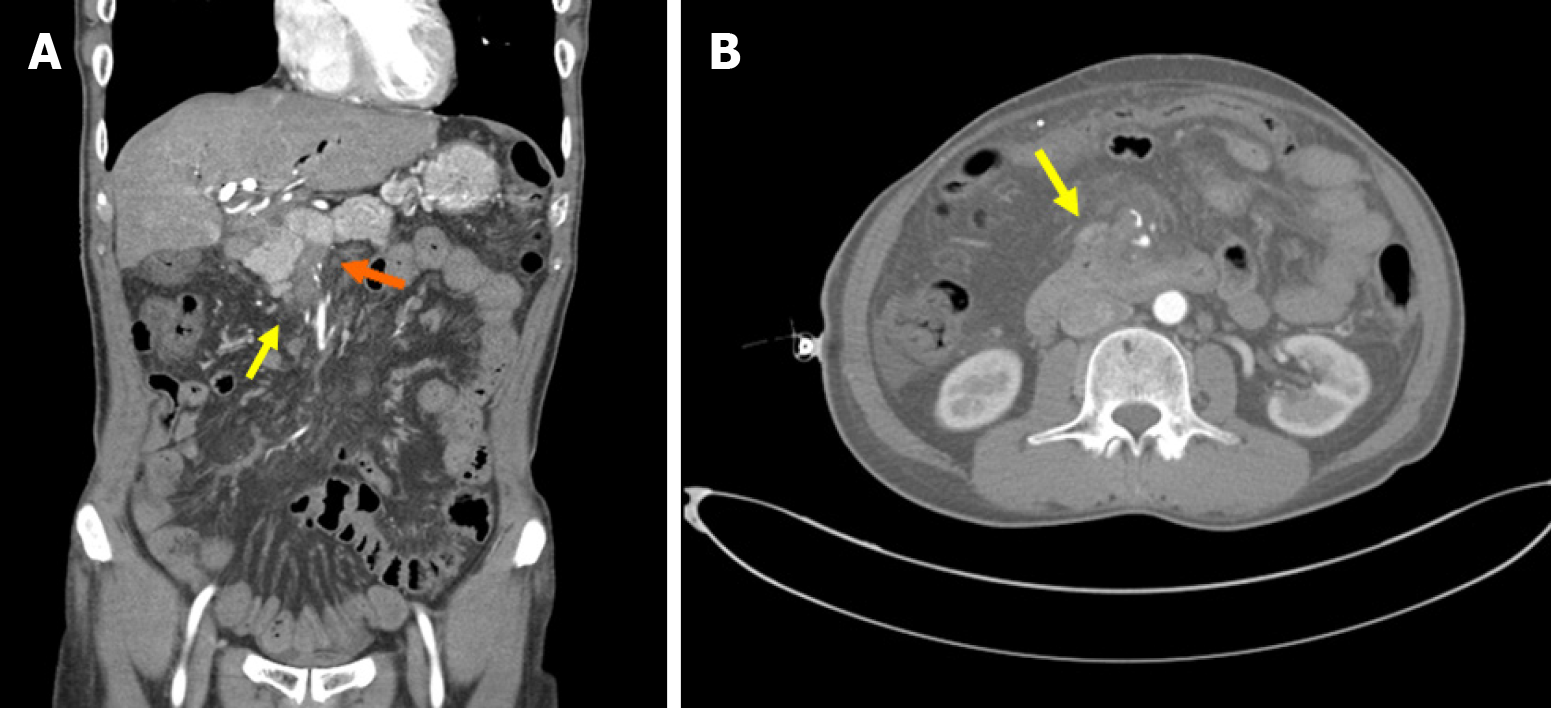

Figure 2 Abdominal computed tomography.

A: On the coronal view, there was portal vein (orange arrow) and superior mesenteric vein thrombus as well as duodenal varix of 3rd portion (yellow arrow); B: On the axial view, there was duodenal varix at the 3rd portion (yellow arrow).